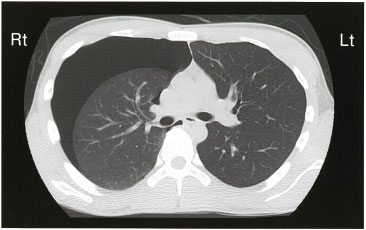

51 Aさん(27歳、男性)は、突然の胸痛と呼吸困難があり、救急外来を受診した。意識は清明。身長179cm、体重63kg、胸郭は扁平である。20歳から1日50本の喫煙をしている。バイタルサインは、体温36.1℃、呼吸数22/分、経皮的動脈血酸素飽和度(SpO2)96%(room air)である。

胸部CTを示す。

Aさんの所見から考えられるのはどれか。

- 酸素吸入が必要である。

- 抗菌薬投与が必要である。

- 右肺野の呼吸音は減弱している。

- 左胸腔内は液体成分で占められている。